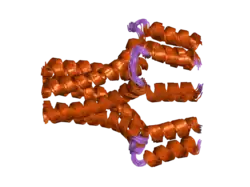

Phospholamban pentamer | |||||||||

Phospholamban, also known as PLN or PLB, is a micropeptide protein that in humans is encoded by the PLN gene.[5] Phospholamban is a 52-amino acid integral membrane protein that regulates the calcium (Ca2+) pump in cardiac muscle cells.[6]

This protein is found as a pentamer and is a major substrate for the cAMP-dependent protein kinase (PKA) in cardiac muscle. In the unphosphorylated state, phospholamban is an inhibitor of cardiac muscle sarcoplasmic reticulum Ca2+-ATPase (SERCA2)[7] which transports calcium from cytosol into the sarcoplasmic reticulum. When phosphorylated (by PKA) - disinhibition of Ca2+-ATPase of SR leads to faster Ca2+ uptake into the sarcoplasmic reticulum, thereby contributing to the lusitropic response elicited in heart by beta-agonists.[8] The protein is a key regulator of cardiac diastolic function. Mutations in this gene are a cause of inherited human dilated cardiomyopathy with refractory congestive heart failure.[9]

When phospholamban is phosphorylated by PKA, its ability to inhibit SERCA2 is lost.[10] Thus, activators of PKA, such as the beta-adrenergic agonist epinephrine (released by sympathetic stimulation), may enhance the rate of cardiac myocyte relaxation. In addition, since SERCA2 is more active, the next action potential will cause an increased release of calcium, resulting in increased contraction (positive inotropic effect). When phospholamban is not phosphorylated, such as when PKA is inactive, it can interact with and inhibit SERCA. Thus, the overall effect of unphosphorylated phospholamban is to decrease contractility and the rate of muscle relaxation, thereby decreasing stroke volume and heart rate, respectively.[11]

PLN has been shown to interact with SLN[16][17] and SERCA1.[17][18][19]